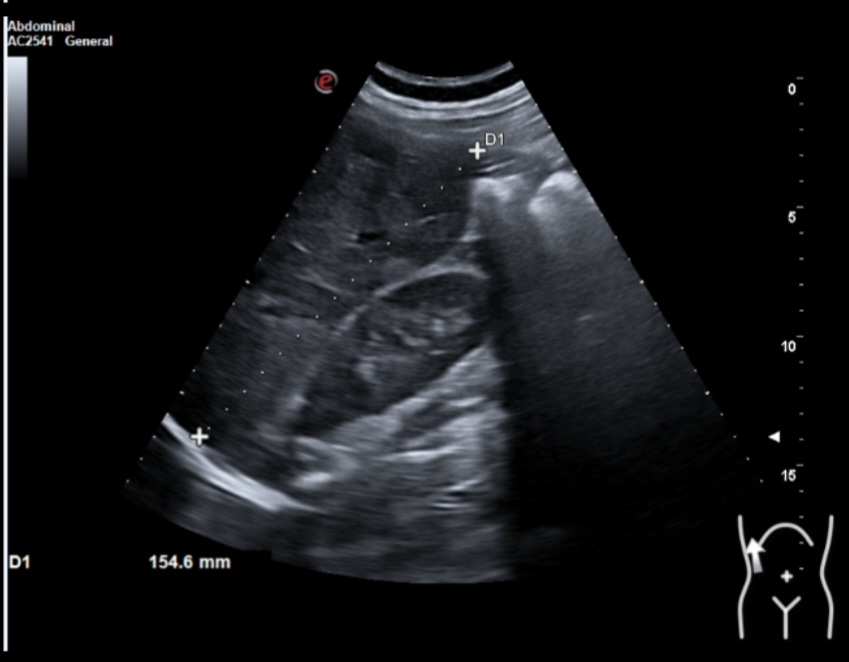

Ecografía clínica: múltiples lesiones en parénquima hepático bien delimitadas de hasta 2 cm, hipoecogénicas, en ambos lóbulos. Tamaño normal del hígado (15 cm) pero bordes obtusos. Vía biliar no dilatada. Vesícula alitiásica. Porta de calibre normal. Área pancreática no visualizada por gas intestinal. Ambos riñones normales. Vejiga vacía, no valorable.

Dados los hallazgos se solicitó ecografía reglada que informaba de múltiples lesiones hepáticas sospechosas y afectación adenopática infradiafragmática. Se recomendó completar estudio mediante TAC estadiaje.